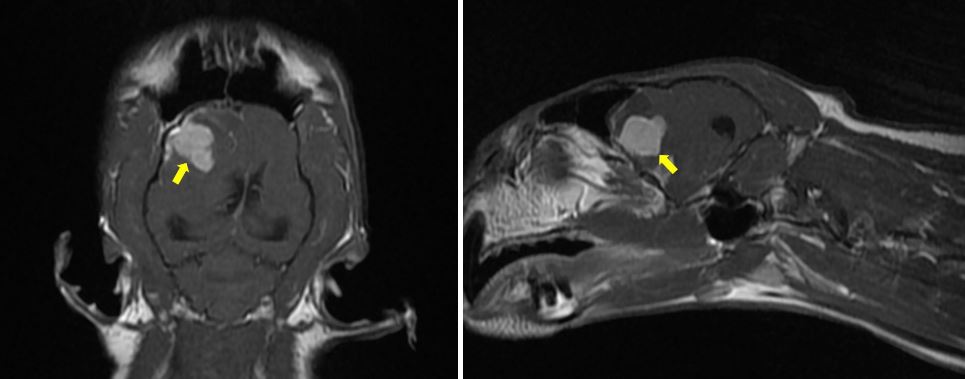

MRI 촬영 결과, 전두엽 근처에서 직경 1cm 정도의 뇌수막종으로 의심되는, 낭종성 변화를 동반한 종괴(노란색 화살표)가 관찰됐습니다.

고양이 뇌수막종은 개에 비해서 경계가 명확해서 주변 뇌조직과 잘 분리되는 경향을 가집니다.¹